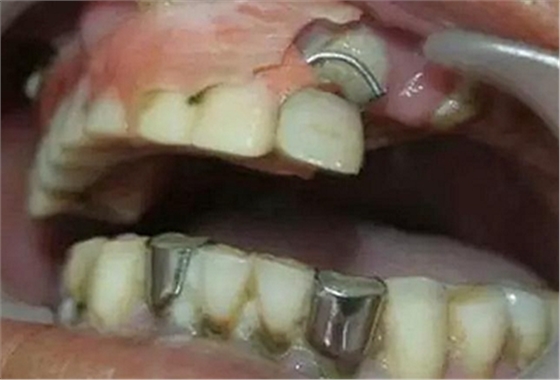

檢查有無不良的義齒或固定冠、橋,有無鄰面充填體的懸突,或不良的正畸矯治器,修復材料的表面是否光潔,有無錯殆、不良習慣、食物嵌塞、解剖異常等(如畸形舌側溝、附著齦過窄、系帶附著異常等)。